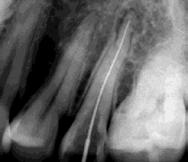

Las Figuras 4-13 son imágenes radiográficas de los dientes de la paciente que presen tan múltiples lesiones periapicales como consecuencia de las necrosis pulpares originadas por la radioterapia. Se realizaron los

tratamientos y retratamientos endodónticos necesarios para preservar los dientes en boca, evitando las exodoncias y por lo tanto minimizando el riesgo de generar osteorradionecrosis.

La Figura 14 muestra la imagen del carcinoma epidermoide de la mucosa yugal antes de la radioterapia. La Figura 15 muestra la radiografía dentoalveolar del incisivo central

Osteorradionecrosis de los maxilares: etiología y prevención

superior izquierdo con diagnóstico de necrosis pulpar y un área radiolúcida periapical extensa.

Las Figuras 16 y 17 muestran el tratamiento endodóntico del incisivo central superior izquierdo. Las Figuras 18 y 19 muestran el tratamiento endodóntico del incisivo central superior derecho. Se puede observar que también se realizó la endodoncia del resto radicular del incisivo central superior derecho pues no se debe realizar la exodoncia del mismo.

La Figura 20 muestra la imagen del carcinoma epidermoide de lengua antes de la radioterapia. Las Figuras 21,22 y 23 muestran las radiografías dentoalveolares del segundo premolar superior derecho con diagnóstico

de necrosis pulpar por radiación ionizante y el tratamiento endodóntico correspondiente.

Las Figuras 24 y 25 son las imágenes de las radiografías dentoalveolares del diente incisivo lateral inferior derecho y las Figuras 26 y 27 del incisivo lateral inferior izquierdo. Ambos dientes afectados de necrosis pulpar con lesiones periapicales por efecto de la radioterapia y los tratamientos endodónticos.